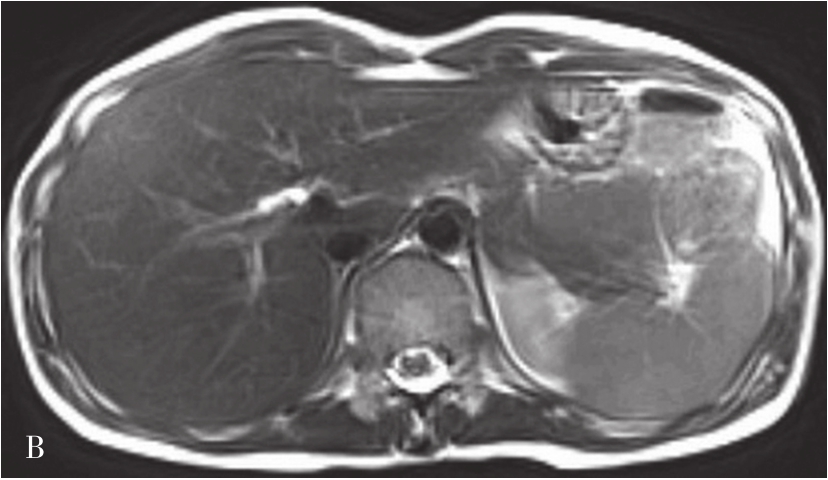

MRI图像,正常肝脏蛋白质含量丰富,自由水含量较少,肝组织的T 1 、T 2 弛豫时间短,T 1 WI呈中等强度的灰阶,与脊髓及胰腺相仿,肝脏信号相对高于脾脏及肌肉(图5-21-40A);T 2 WI则低于脾脏(图5-21-40B)。肝内血管和胆管在T 1 WI通常表现为低信号,T 2 WI胆管呈高信号。第二肝门处3根静脉在肝实质衬托下呈“鸡爪状”向腔静脉聚集。正常肝总管及左右肝管一般不被显示,在扩张情况下表现为门脉前方与之伴行的管道结构,信号略高于门脉。MRI上观察肝脏是否正常,一般要从肝脏形态、大小、信号是否异常,肝的分叶分段是否俱全、轮廓是否光整、表现是否光滑、肝裂是否增宽、质地是否细腻、信号是否均匀、血管纹理是否走行自然等多方面去评价。

图5-21-40 正常T 1 WI及T 2 WI图像

A.正常T 1 WI图像;B.正常T 2 WI图像